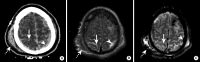

Intracranial hemorrhage is common and is caused by diverse pathology, including trauma, hypertension, cerebral amyloid angiopathy, hemorrhagic conversion of ischemic infarction, cerebral aneurysms, cerebral arteriovenous malformations, dural arteriovenous fistula, vasculitis, and venous sinus thrombosis, among other causes. Neuroimaging is essential for the treating physician to identify the cause of hemorrhage and to understand the location and severity of hemorrhage, the risk of impending cerebral injury, and to guide often emergent patient treatment. We review CT and MRI evaluation of intracranial hemorrhage with the goal of providing a broad overview of the diverse causes and varied appearances of intracranial hemorrhage.